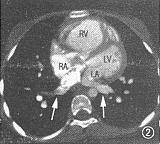

图1~6 为同一病例,部分型肺静脉异位连接(心脏型)。图1示右上肺静脉(短箭头)引流入右心房(RA),左上肺静脉(长箭头)引流入左心房(LA),房间隔缺损巨大。图2示两下肺静脉(箭头)分别引流入左右心房。RV:右心室;LV左心室。图3示下腔静脉肝段缺如:肝脏水平未见下腔静脉显影,半奇静脉粗大(箭头)。图4为表面阴影显示法三维重建,示右侧上下肺静脉(白箭头)均引流入右心房,左侧上下肺静脉(黑箭头)均引流入左心房。SVC:上腔静脉。图5为导管自下腔静脉经奇静脉入右心房经右心室至右肺动脉造影:右肺静脉(黑箭头)引流入右心房(白箭头)。图6为左肺动脉造影,示左肺静脉(白箭头)引流入左心房(白三角箭头),对比剂经房间隔缺损(黑箭头)分流入右心房

2例手术患者,完全型及部分型肺静脉异位连接各有1例。其中部分型肺静脉异位连接者EBCT显示右侧肺静脉引流入右心房,而左侧肺静脉正常回流入左心房,伴有II孔型房间隔缺损、肺动脉高压、下腔静脉肝段缺如。术前心血管造影检查及手术所见均与EBCT相同(图1~6)。1例完全型肺静脉异位连接,术前造影示单发右位心、右室双出口、肺动脉瓣及瓣下狭窄、房室间隔缺损、双上腔静脉,但心室造影未能明确肺静脉引流位置,遂行EBCT检查。EBCT除显示上述畸形外,尚显示右位主动脉弓及完全型肺静脉异位连接。